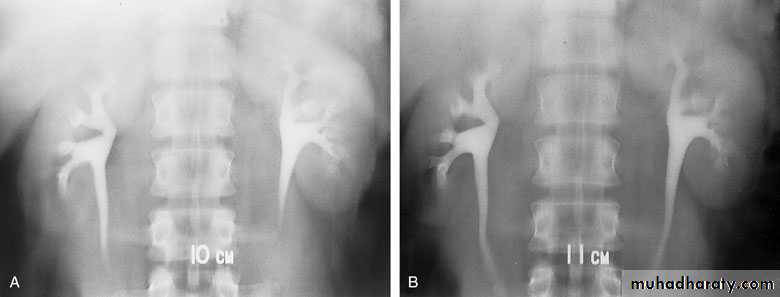

Intravenous urography (IVU)

- After a plain film, iodine-containing contrast medium is injected intravenously and serial films are taken to follow its excretion by the kidneysThe nephrogram phase - on the initial film 1-3 minutes after injection, contrast medium is in the glomeruli and proximal tubules so that a clear image of the renal outline is obtained

The pyelogram phase - subsequent excretion of contrast medium outlines the collecting systems, renal pelvis, ureter and bladder, showing any structural abnormalities or filling defects